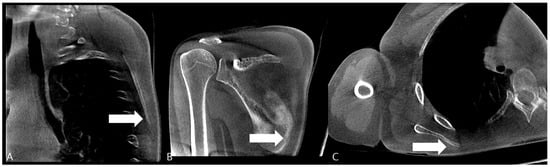

Ultrasonographic Diagnosis and Computed Tomographic Confirmation of a Scapular Body Stress Fracture in an Elite Boxer: A Case Report

Background and Clinical Significance: Scapular stress fractures are exceptionally rare in athletes and are notoriously difficult to diagnose due to their subtle presentation and poor sensitivity on initial radiographs. This case report describes the diagnostic challenge of a scapular body stress fracture in an elite boxer who initially presented with wrist pain. Case Presentation: A 19-year-old right-hand-dominant female elite boxer presented with a three-month history of bilateral wrist pain. Initial examination and MRI were consistent with a triangular fibrocartilage complex (TFCC) injury. Despite conservative management, her symptoms persisted, and she subsequently developed mechanical right shoulder pain and a sensation of instability. Physical examination revealed scapular dyskinesis, with a positive push-up test and weakness on punch protraction. Plain radiographs of the scapula were unremarkable. Point-of-care musculoskeletal ultrasound (MSK US) identified a cortical irregularity at the medial scapular border. A subsequent computed tomography (CT) scan obtained at three-month follow-up definitively confirmed a stress fracture at this site. Treatment focused on scapular stabilization via prolotherapy and activity modification, leading to symptomatic resolution and a successful return to sport. Conclusions: This case underscores the importance of evaluating the entire kinetic chain in athletes presenting with focal complaints. It demonstrates the utility of MSK US as an effective initial screening tool for cortical stress fractures and highlights the necessity of CT for definitive confirmation. Clinicians should maintain a high index of suspicion for scapular stress injuries in overhead athletes with unexplained shoulder dysfunction. Full article

Figure 1